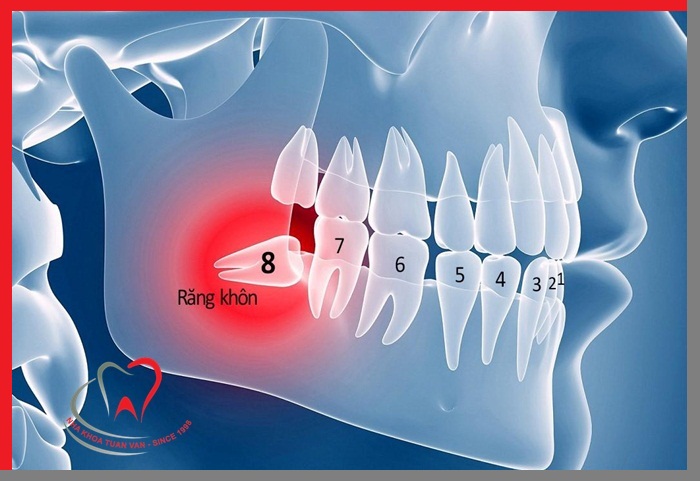

Răng khôn (còn gọi là răng số 8) là răng mọc cuối cùng của hàm, thông thường mọc ở người trong độ tuổi 17 đến 25. Răng khôn gây ra nhiều phiền toái: đau, nhức, ảnh hưởng tới chức năng ăn nhai.

Răng khôn thường mọc không như bạn mong muốn

Răng khôn mọc gây đau đớn, khó chịu

Răng khôn mọc lệch đâm vào chân răng bên cạnh